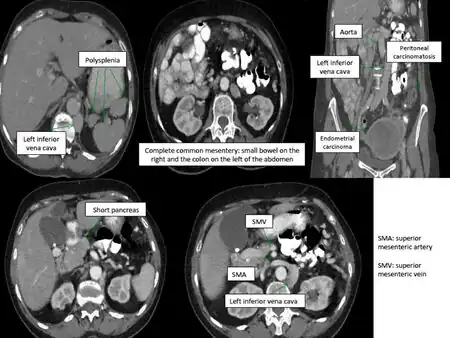

Situs ambiguus is a rare congenital defect in which the major visceral organs are distributed abnormally within the chest and abdomen. Clinically heterotaxy spectrum generally refers to any defect of Left-right asymmetry and arrangement of the visceral organs; however, classical heterotaxy requires multiple organs to be affected. This does not include the congenital defect situs inversus,[1] which results when arrangement of all the organs in the abdomen and chest are mirrored, so the positions are opposite the normal placement. Situs inversus is the mirror image of situs solitus, which is normal asymmetric distribution of the abdominothoracic visceral organs. Situs ambiguus can also be subdivided into left-isomerism and right isomerism based on the defects observed in the spleen, lungs and atria of the heart.

There are a variety of clinical manifestations of situs ambiguus. Acute symptoms can be due to both cardiac and non-cardiac defects. Cyanosis or blue skin coloration, primarily affecting the lips and fingernails, can indicate a systemic or circulatory issue. Poor feeding, failure to thrive, and rapid shallow breathing may also be observed due to poor circulation. Upon examination, arrhythmia and heart murmur may raise further suspicion of a cardiac abnormality. Non-cardiac symptoms include impairments of the liver and gastrointestinal tract. Biliary atresia, or inflammation and destruction of the bile ducts, may lead to jaundice. Vomiting and swelling of the abdominal region are features that suggest improper positioning of the intestines. Poor positioning of the intestine also makes it more prone to blockage, which can result in numerous chronic health issues.[4] Asplenia and polysplenia are also possible features of heterotaxy syndrome.[6]

Abdominal organs, including the liver, stomach, intestinal tract, and spleen may be randomly arranged throughout the left-right axis of the body. Distribution of these organs largely dictates treatment, clinical outcomes, and further evaluation.

Isomeric patients often experience disruptions to splenic development during embryogenesis, resulting in an overall lack a spleen (asplenia) or development of many spleens (polysplenia). Asplenia is most often observed in patients with right atrial isomerism. Polysplenia results in 90% of patients with left atrial isomerism. Although they have many spleens, each is usually ineffective resulting in functional asplenia. Rarely, left atrial isomeric patients have a single, normal, functional spleen. Patients lacking a functional spleen are in danger of sepsis and must be monitored.[2]

- More rarely, the head of the pancreas fails to form

- Interrupted inferior vena cava,

- Bilateral superior or inferior venae cavae

- Intrahepatic interruption of the inferior vena cava with connection to the azygos or hemiazygos veins